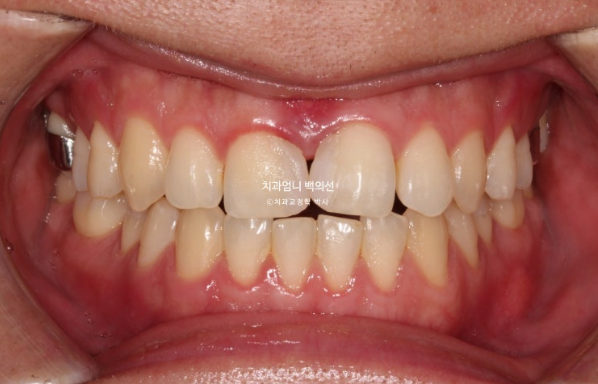

After wearing the aligners for another 3 months from December 2024 to February 2025, the treatment was completed.

You can see a well-aligned midline and a good bite.

If the molar bite is not perfect, we do not finish treatment.

This is how it looks with the wire retainer in place.

Now let’s compare before and after.

Treatment began in January 2023, and the time spent on arch expansion and waiting for bone to fill in was 6 months. The actual orthodontic treatment period while wearing Invisalign aligners was from July 2023 to March 2025, for a total of 1 year and 8 months.

In the front teeth area, once the open bite and reverse bite were corrected, a stable bite was created.